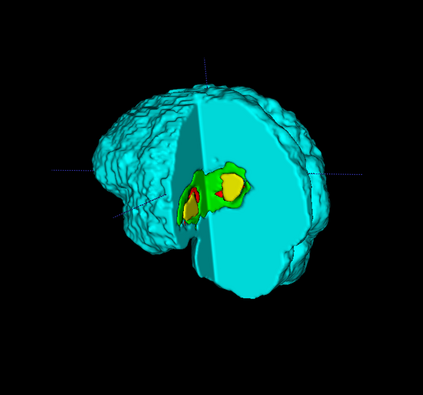

Segmentation of brain tumor from magnetic resonance imaging (MRI) is a vital process to improve diagnosis, treatment planning and to study the difference between subjects with tumor and healthy subjects. In this paper, we exploit a convolutional neural network (CNN) with hypercolumn technique to segment tumor from healthy brain tissue. Hypercolumn is the concatenation of a set of vectors which form by extracting convolutional features from multiple layers. Proposed model integrates batch normalization (BN) approach with hypercolumn. BN layers help to alleviate the internal covariate shift during stochastic gradient descent (SGD) training by zero-mean and unit variance of each mini-batch. Survival Prediction is done by first extracting features(Geometric, Fractal, and Histogram) from the segmented brain tumor data. Then, the number of days of overall survival is predicted by implementing regression on the extracted features using an artificial neural network (ANN). Our model achieves a mean dice score of 89.78%, 82.53% and 76.54% for the whole tumor, tumor core and enhancing tumor respectively in segmentation task and 67.90% in overall survival prediction task with the validation set of BraTS 2018 challenge. It obtains a mean dice accuracy of 87.315%, 77.04% and 70.22% for the whole tumor, tumor core and enhancing tumor respectively in the segmentation task and a 46.80% in overall survival prediction task in the BraTS 2018 test data set.